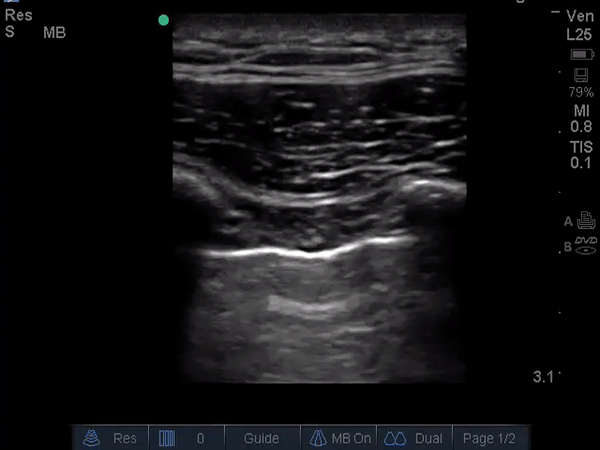

The ultrasound m-mode image is an example of a ‘lung point’ sign that

is highly specific for diagnosing a pneumothorax (image 1). Lung

sliding is seen as artifact created by the visceral-parietal pleural

interface and is seen in the contralateral lung as displayed in video 1. The right lung is shown in video 2

and lung sliding is not seen because of the pneumothorax. This patient

Lung sliding is seen in a lung without a pneumothorax, but may not be

appreciable in all patients. The use of m-mode makes this finding more

apparent. A normal lung appears as a ‘seashore sign’ on m-mode while a

pneumothorax will not show any lung sliding and will appear as a

‘barcode sign’. When both the barcode and seashore signs are seen on an

m-mode image in succession as seen in image 1, it is termed a lung

point, denoting the edge of the pneumothorax.